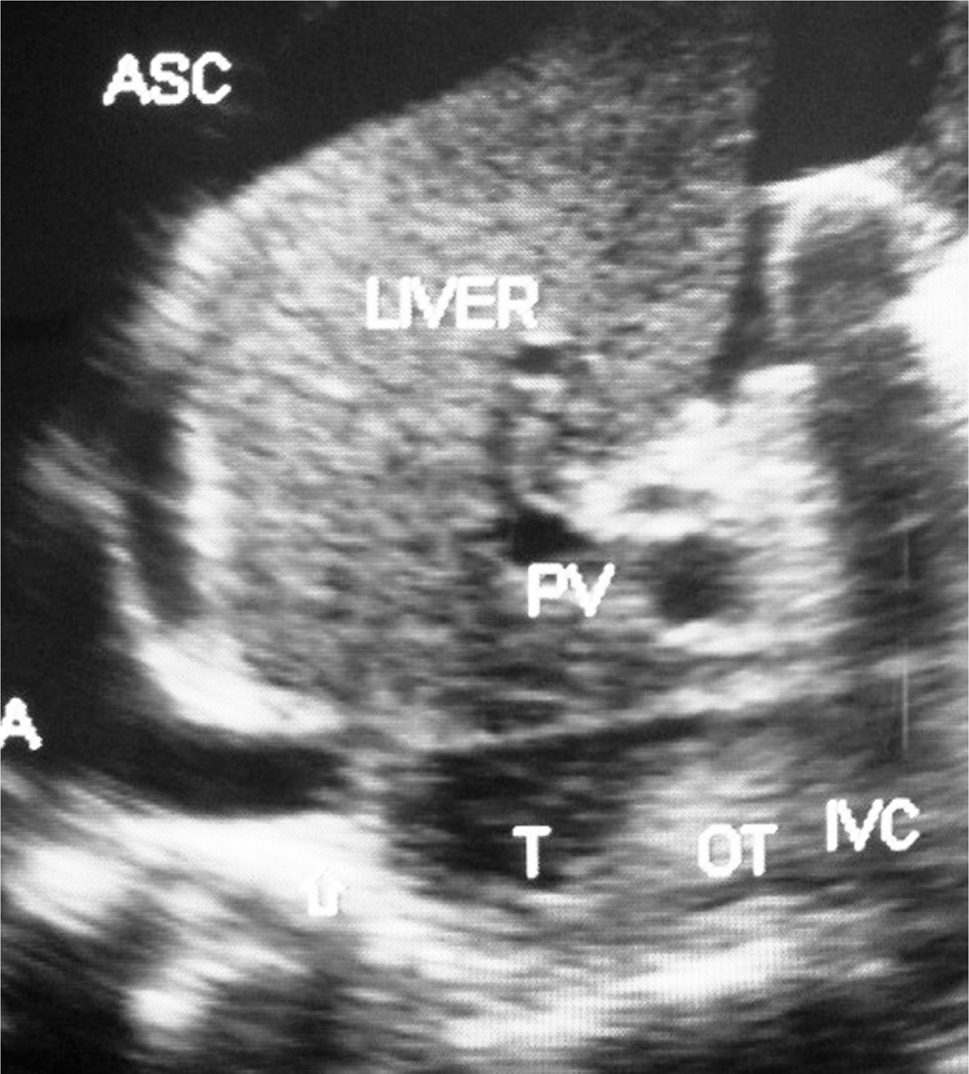

Fig 3

Figure 3. Hepatic vena cava syndrome: Ultrasonography of a young patient with ascites showing localized stenosis of upper segment of IVC with distal dilated segment of the IVC filled with recent and old organized thrombi. ASC, ascites; IVC, inferior vena cava; OT, organized thrombus; RA, right atrium; T, thrombus. (Copyright: Santosh Man Shrestha).

The initial lesion or the thrombus formed during severe AE may extend into HV outlets, resulting in HVOO with sudden development of ascites (Figure 3). Severe AE is likely to develop in persons with poor nutrition or history of alcohol abuse precipitated by puerperal sepsis, chronic bacterial diarrhea, or surgical operation (72, 73). Fever and jaundice usually preceded ascites which is associated with neutrophil leukocytosis, elevated level of C-reactive protein (CRP), and or bacteremia. Ascites in HVCS is invariably associated with bacterial peritonitis (6). About 15% of patients develop pleural effusion (74). US/CD examination (75) and laboratory tests that include total and differential white blood cells (WBC), culture of blood and ascitic fluid, and estimation of CRP are diagnostic of ascites from severe acute/AE of HVCS. This condition responds to treatment with high-dose oral antibiotic for 6–8 weeks, salt restriction, and diuretics.